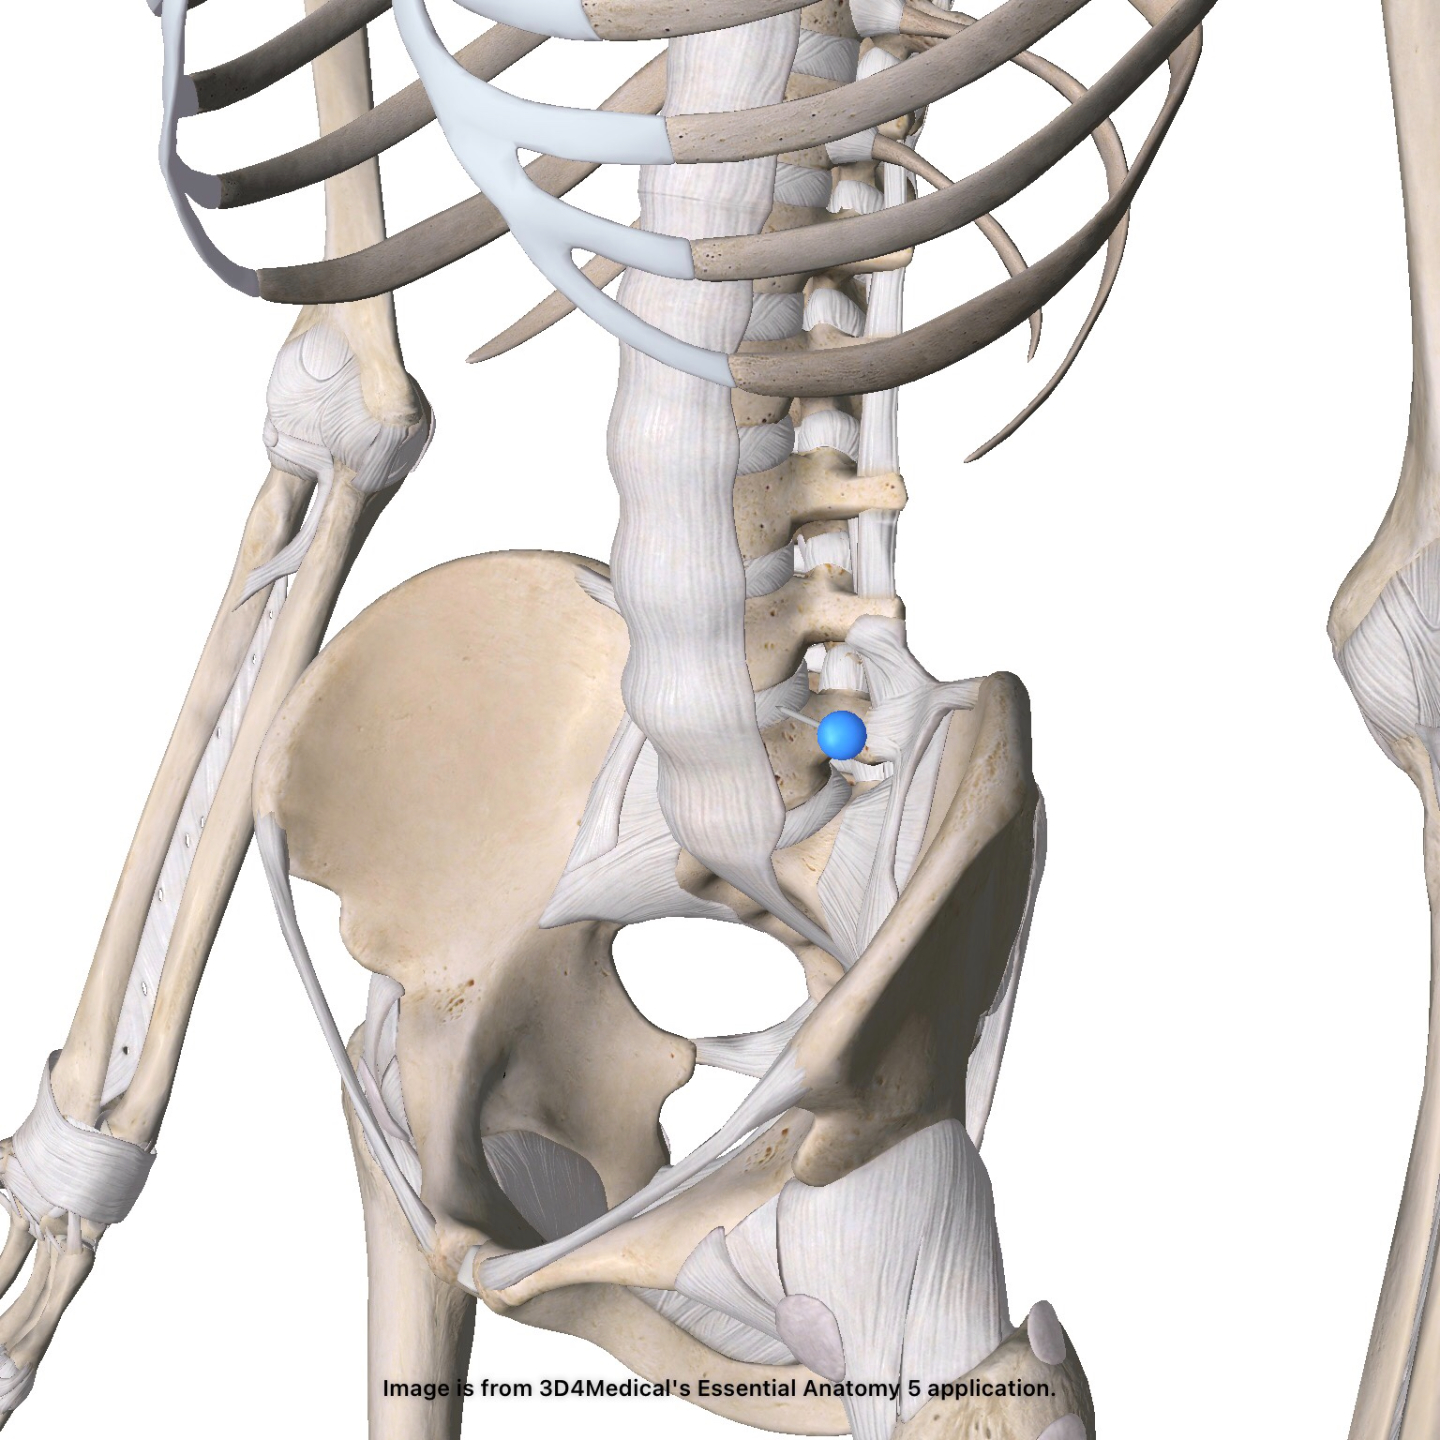

Back Injuries

Check out our one-of-a-kind diagnostic dashboard! Learn more about multiple orthopedic back injuries - the who, what, when, where, and how's.

Diagnostic Dashboard

Spondylolysis

Low Back Pain